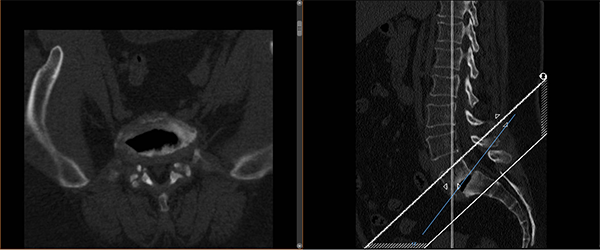

術(shù)前影像

根據(jù)覃阿姨門診腰椎磁共振顯示:腰5椎體I度滑脫伴雙側(cè)椎弓峽部裂,腰5骶1椎間盤突出合并椎管狹窄,我院脊柱外科主任胡朝暉博士及其團(tuán)隊(duì)討論研究后認(rèn)為,患者身型重度肥胖,140cm的身高體重高達(dá)72公斤,BMI指數(shù)達(dá)36.7,屬于超重范圍,開刀手術(shù)難度將升級,存在易出血多、感染幾率升高、術(shù)口相對難愈合等風(fēng)險(xiǎn),但內(nèi)鏡下腰椎融合手術(shù)較傳統(tǒng)開放手術(shù)相比,僅需要5個(gè)1.5cm的皮膚切口,具有創(chuàng)傷更小、出血更少、切口感染概率低、術(shù)后恢復(fù)快、病人術(shù)后疼痛輕等優(yōu)點(diǎn),因此內(nèi)鏡下腰椎融合手術(shù)更適合覃阿姨。